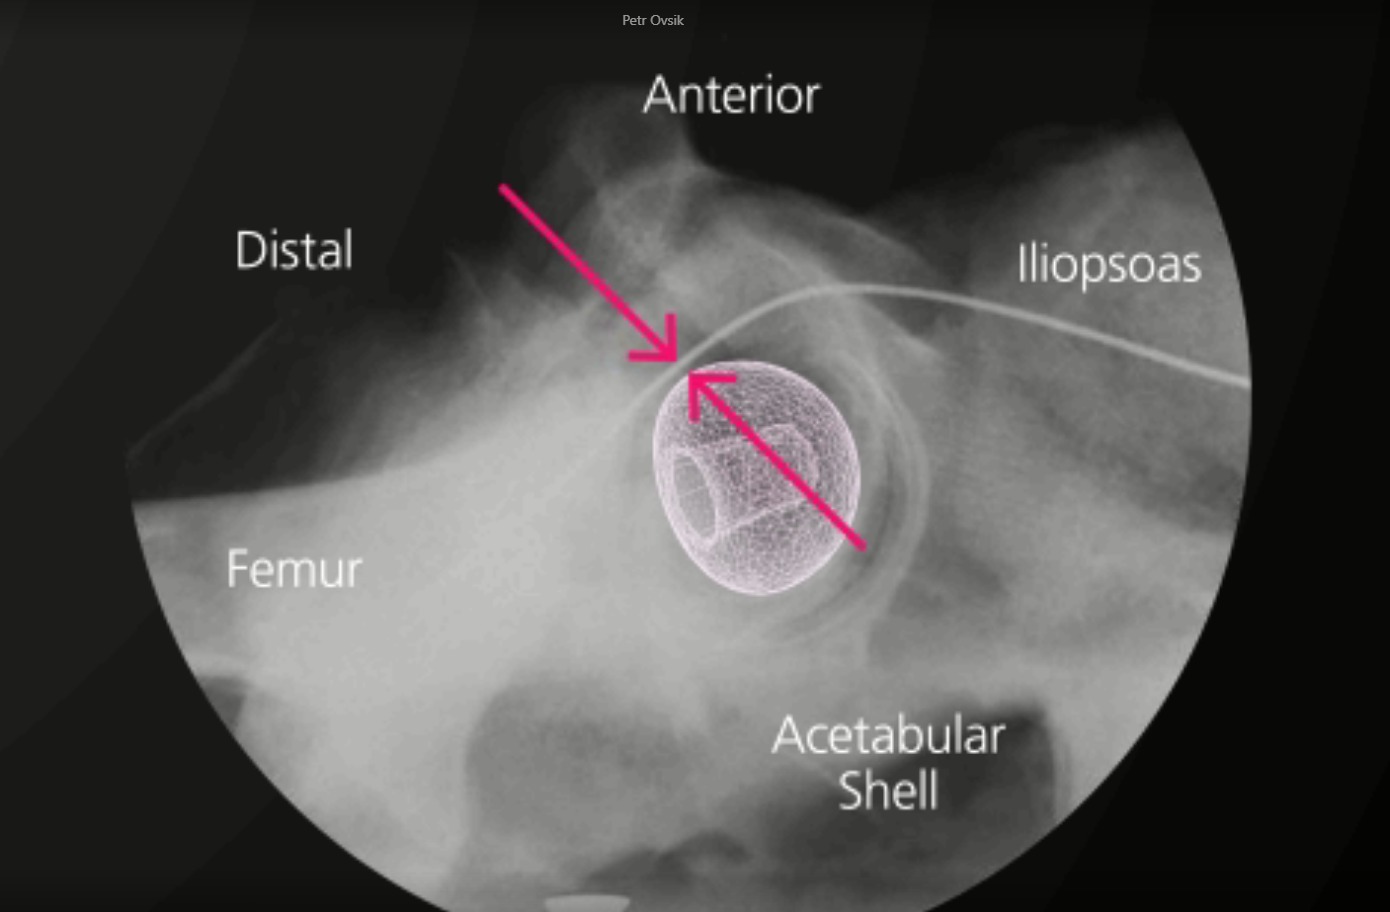

BIOLOX CONTOURA® is a contoured ceramic femoral head mimicking the anatomical shape of the proximal femur.

With the BIOLOX CONTOURA®, the large-diameter profile of a conventional implant is retained in the hemispherical portion above the equator. However, the distal portion of the femoral head below the equator is contoured using a smaller radius to reduce the volume of material exposed to the soft tissue.

An overlay of a 36mm BIOLOX CONTOURA® head and a 32mm conventional ceramic femoral head shows the volume reduction of BIOLOX CONTOURA®. See volume reduction here.